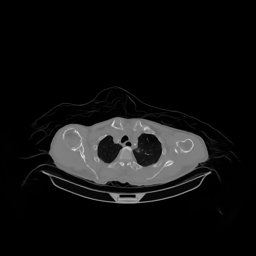

III-D Real Clinical Data Experiment

The experimental results on clinical head data are shown in Fig. 4. The reference images were reconstructed using the fast iterative shrinkage-thresholding algorithm (FISTA) with total variation regularization from non-truncated projection data. In the WCE reconstructions (Fig. 4(b)), severe truncation prevents accurate recovery of anatomical structures outside the FOV. Despite being trained solely on simulated data with a domain gap, all deep learning models can restore a substantial portion of the missing anatomy. Among them, the diffusion-based methods recover soft-tissue boundaries more faithfully than the conventional deep learning approach FBPConvNet, highlighting their stronger image generation capability. However, cDDPM reconstructions exhibit more noticeable noise than those from other methods, consistent with the simulated data results. The patchDiffusion model introduces artifacts within the FOV, likely due to its patch-wise processing strategy. While I2SB shares the same limitations as other diffusion models in perfectly restoring soft-tissue detail, it produces fewer residual noise patterns and fewer artifacts within the FOV boundaries. Overall, Fig. 4 demonstrates the strong efficacy of I2SB in reconstructing real CBCT data.